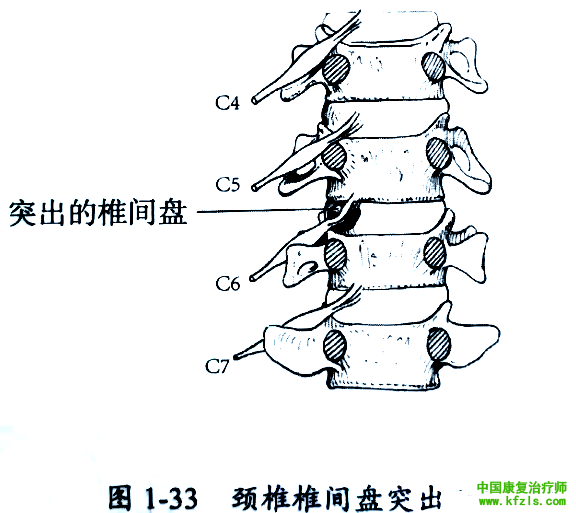

突出的椎间盘从上方压迫自椎间盘上方发出并行经椎旁椎间孔的神经根,并导致相应神经节段受累。如 C5和C6椎间盘突出将从上方压迫C6神经根(图1-33 )。